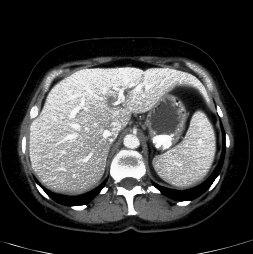

In clinical routine, manual or semi-manual segmentation techniques are applied to interprete CT and MRI images that have been acquired in the diagnosis of the liver. These techniques, however, are subjective, operator-dependent and very time-consuming. In order to improve the productivity of radiologists, computer-aided methods have been developed in the past. However, an automated robust segmentation of combined liver and lesion remains still an open problem because of challenges as a low-contrast between liver and lesion, different types of contrast levels (hyper-/hypo-intense tumors), abnormalities in tissues (such as after surgical resection of metastasis), size and varying number of lesions. As shown in figure 1 the heterogeneity in liver and lesion contrast is very large among subjects. Different acquisition protocols, differing contrast-agents, varying levels of contrast enhancements and dissimilar scanner resolutions lead to unpredictable intensity differences between liver and lesion tissue. This complexity of contrast differences make it difficult for intensity-based methods to generalize to unseen test cases from different clinical sites. In addition, the varying shape of lesions due to irregular tumor growth and response to treatment (i.e surgical resection) reduce efficiency of computational methods that make use of prior knowledge on lesion shape.

Figure 1: Liver and liver lesions slices in CT and diffusion weighted DW-MRI as well as the corresponding histogram for liver and lesions pixels in the respective modality. The shape, size and level of contrast vary for different lesions. As the histograms indicate, there is a significant overlap between liver and lesion intensities, leading to a low overall contrast.